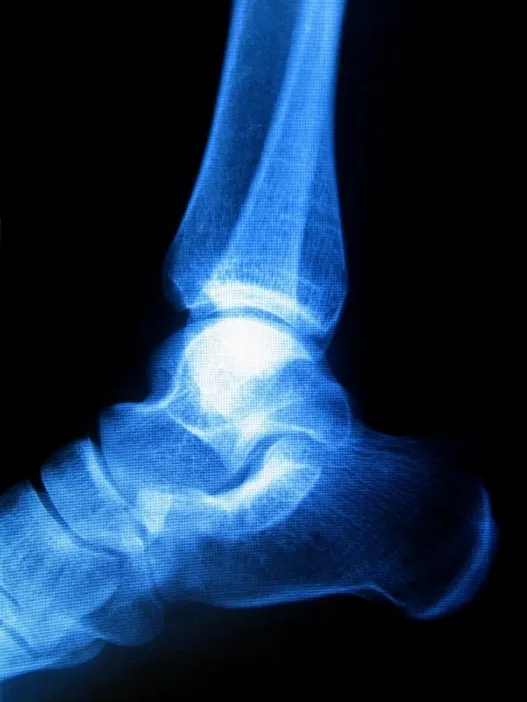

Sometimes known as “pump bump” because of its prevalence among women who wear pump-style shoes, Haglund's deformity can occur in one or both of the feet. If you are suffering from Haglund's deformity you will most likely have noticed a bony enlargement at the back of the heel. This inflammation is caused when the bursa, a fluid­ filled sac between the Achilles tendon and your heel bone, becomes irritated. Other signs of Haglund's deformity include pain where the Achilles tendon and the heel meet, swelling, and redness.

While genetic factors influence your likelihood to develop Haglund’s deformity (high arches, a tight Achilles tendon), stiff shoes are also a major risk factor.